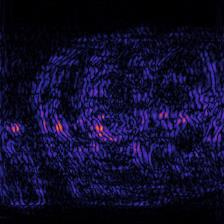

Recently, deep neural networks have greatly advanced undersampled Magnetic Resonance Image (MRI) reconstruction, wherein most studies follow the one-anatomy-one-network fashion, i.e., each expert network is trained and evaluated for a specific anatomy. Apart from inefficiency in training multiple independent models, such convention ignores the shared de-aliasing knowledge across various anatomies which can benefit each other. To explore the shared knowledge, one naive way is to combine all the data from various anatomies to train an all-round network. Unfortunately, despite the existence of the shared de-aliasing knowledge, we reveal that the exclusive knowledge across different anatomies can deteriorate specific reconstruction targets, yielding overall performance degradation. Observing this, in this study, we present a novel deep MRI reconstruction framework with both anatomy-shared and anatomy-specific parameterized learners, aiming to "seek common ground while reserving differences" across different anatomies.Particularly, the primary anatomy-shared learners are exposed to different anatomies to model flourishing shared knowledge, while the efficient anatomy-specific learners are trained with their target anatomy for exclusive knowledge. Four different implementations of anatomy-specific learners are presented and explored on the top of our framework in two MRI reconstruction networks. Comprehensive experiments on brain, knee and cardiac MRI datasets demonstrate that three of these learners are able to enhance reconstruction performance via multiple anatomy collaborative learning.